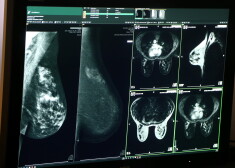

Šodien, 21.februārī, bija iespēja klātienē apskatīt mamogrāfijas un stereotaktiskās biopsijas izmeklējumu iekārtu, kā arī uzskatāmi pārliecināties par to darbību, iegūtajiem attēliem un to kvalitāti.

Tagad ikvienai Rīgas Austrumu klīniskās universitātes slimnīcas stacionārā Latvijas Onkoloģijas centrs pacientei, iepriekš pierakstoties, būs iespēja veikt izmeklējumus ar jaunām, modernām un augstas izšķirtspējas iekārtām. Mamogrāfijas iekārta “AMULET Innovality”, kā arīstereotaktiskās biopsijas izmeklējumu iekārta “Affirm Prone Breast Biopsy System” ir paredzētas pacientes kompleksai izmeklēšanai. Līdz šim uzreiz pēc jauno iekārtu uzstādīšanas, pielāgojot programmatūru un veicot mediķu apmācību, Rīgas Austrumu klīniskajā universitātes slimnīcā plānveida un zaļā koridora pacientēm jau tika veikti šādi plaša spektra izmeklējumi.

Viens no mamogrāfiem ir diagnostiskais mamogrāfs, kuram ir visaugstākā izšķirtspēja krūts vēža diagnostikai. Iekārta ir aprīkota arī ar tomosintēzi – krūts dziedzera uzņēmumi no vairākiem leņķiem, lai labāk ieraudzītu audu izmaiņas uz dziedzeraudu fona. Otra pilnīgi jauna iespēja ir veikt mamogrāfiju ar kontrastvielu un pēc tam subtrakciju, kas nodrošina konkrēta veidojuma labāku vizualizāciju. Rīgas Austrumu klīniskā universitātes slimnīca šo iekārtu iegādājās par 222 555 eiro (bez PVN) par pašu līdzekļiem.

Otrs mamogrāfs ir „specializētā stereotaktiskās mamogrāfijas iekārta ar vakuuma biopsijas aprīkojumu, kas nodrošina 2D/3D attēlveidošanu un 360 grādu pieeju pacientam guļus stāvoklī uz vēdera". Tā cena iepirkuma rezultātā ir 270 404,75 eiro. Valsts finansēja iekārtas iegādi 250 000 eiro apmērā, savukārt atlikušo naudas summu samaksāja Rīgas Austrumu klīniskā universitātes slimnīca.

Ilze Eņģele: „Krūts audzēju diagnosticēšanai tiek izmantota mamogrāfija, mamogrāfija ar kontrastvielu, tomosintēze, stereotakse, rezultātā operācijas kļūs daudz saudzīgākas. Ja parastā 2D mamogrāfijā krūti redzam kā grāmatu - no vāka līdz vākam, tad tomosintēze ir tik precīzs izmeklējums, it kā mēs krūti šķirstītu it kā pa lapai. Vienu pēc otras, ļoti precīzi. Tieši šis precīzais izmeklējums ļauj vēzi atklāt ļoti agrīni un atklāšanas brīdī jau atbrīvot krūti no aizdomīgā veidojuma bez speciālas operācijas.”